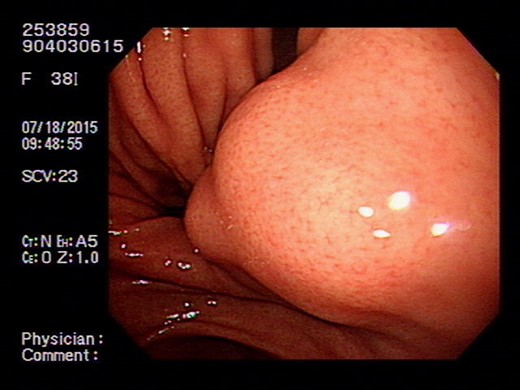

Heterotopic pancreas is a congenital anomaly with a reported prevalence of 0.5–13.7%. The most common locations are the upper gastrointestinal tract such as the stomach, duodenum and proximal jejunum. The less common sites are the esophagus, ileum and biliary tree. The diagnosis of heterotopic pancreas prior to surgery is difficult as it is generally asymptomatic. Besides, it also shares common features of the submucosal lesion under endoscopic (Fig. 4) or computed tomography examination. Although so, pathological changes similar to that of a normal pancreas (acute or chronic pancreatitis, cystic degeneration, malignant changes) are possible [4, 5]. Other than that, symptoms due to its anatomical position or tenderness resulting from the secretion of hormones and enzymes could all necessitate surgical interventions. By reviewing works of literature, we are able to gather some clues which might help us differentiate HP from other lesions before a treatment strategy is modulated. On conservative evaluations, a study conducted by Li et al. suggested that for masses <3 cm, a long diameter to short diameter ratio (LD/SD) greater than 1.29, enhancement value of >27.50 HU, enhancement ratio to pancreas of >0.72 are critical features [6]. Besides that, another study by Maryam et al. describes the MR imaging appearance of heterotopic pancreas mimics orthotopic pancreas. Characteristics of high signal intensity of the pancreas at T1-weighted imaging is useful for differentiation. Other than that, T2-weighted and MR cholangiopancreatographic images could help identify rudimentary or dilated ducts in the heterotopic pancreas to aid in differentiations [7]. Although endoscopic findings of central dimpling or umbilication which corresponds to an opening of a duct are the typical endoscopic finding for heterotopic pancreas, Haetaek et al. reported that it is seen in only 1/3 of cases. However, by using magnifying endoscopy with narrow band imaging, they can identify microscopic opening in more than 80% of lesions without a macroscopic opening, which suggests the possible usefulness of this method in predicting the diagnosis of heterotopic pancreas [8]. As for intervention approaches, endoscopic ultrasonographic fine needle aspiration (EUS-FNA) was reported to have a high sensitivity but somewhat limited diagnostic accuracy due to the limited quantity of tissue sample. A new technique of incorporating endoscopic submucosal dissection known as submucosal endoscopy with mucosal flap (SEMF) which could directly visualize the tumor or perform core biopsies has reported specific features of heterotopic pancreas as ‘yellow, cloudy, and soft with small nodule appearance similar to the pancreas.’ This endoscopic visualized features (EVF) could provide clues for the diagnosis of heterotopic pancreas. If uncertain, this technique could also provide the convenience of core biopsy samples for diagnosis prior to surgeries [3].

Gastrointestinal stromal tumor (GIST) under ultrasonography also shares similar feature by arising from the fourth layer of the gastric wall.